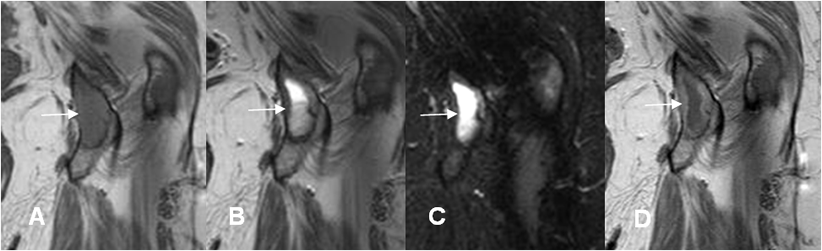

Fig 126 F. Granulomatosis agresiva.

A: RM coronal en T1, B: RM coronal en T2 , C: RM coronal en STIR y D: RM coronal en T1 con contraste. Igual paciente anterior. La imagen del ramo isquiopúbico muestra consistencia quística y realce periférico del contraste.